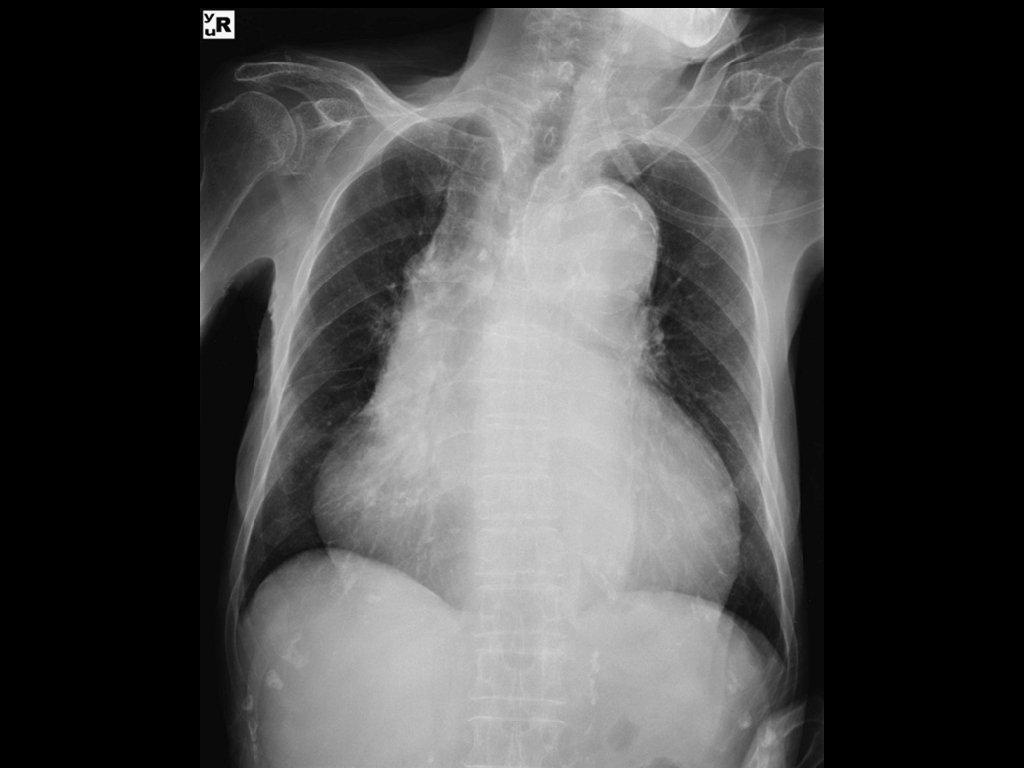

Imaging: • CXR is commonly performed in the evaluation of ED patients with chest pain. • Most patients with ACS have a normal CXR. • Useful to exclude other conditions such as pneumonia and pneumothorax.

Diagnosis: • ECG mostly non specific or may show a STEMI as a result of dissection of coronary ostia. • CXR may shows widened mediastinum (61%) or abnormal aortic contour (50%). • Normal x-ray does not rule out the diagnosis. • CTA is the test of choice.

Diagnosis: • Ill appearing, septic and febrile. • CXR may show left side pleural effusion and mediastinal air. • CT Chest will help in defining injury.